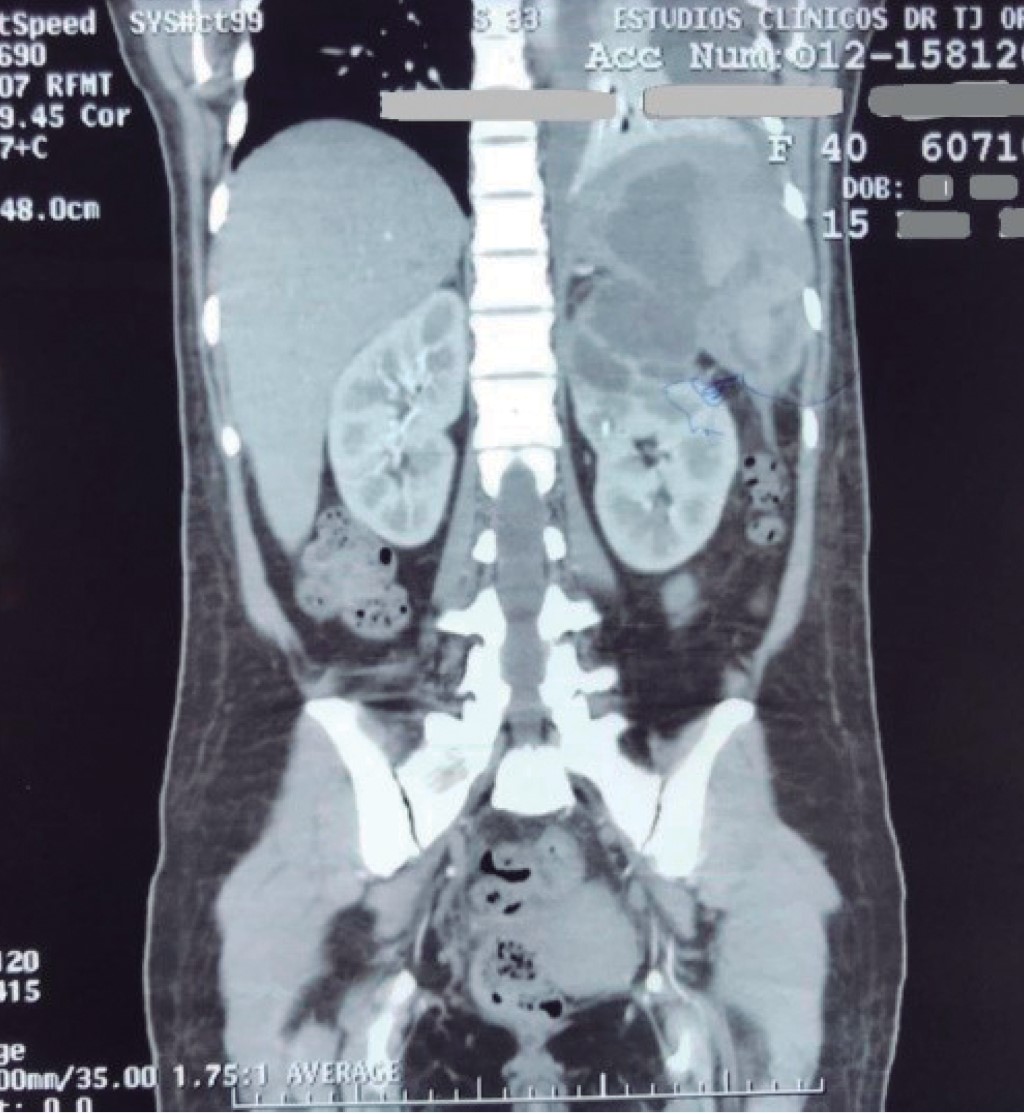

Al ingresar a nuestro hospital se encontraba consciente, signos vitales con presión arterial de 90/60 mmHg, frecuencia cardiaca de 92 latidos por minuto, frecuencia respiratoria de 18 respiraciones por minuto, oximetría periférica con saturaciones al aire ambiente de 90%, temperatura a su ingreso de 37.6 oC que durante su manejo en urgencias en promedio se encontraba en 38 oC. A la exploración física se encontró hipoventilación basal de pulmón izquierdo, dolor en hipocondrio izquierdo y epigastrio, sin irritación peritoneal ni resistencia muscular, con resto de exploración física sin alteraciones ni datos relevantes para el cuadro clínico. Con exámenes de laboratorio con hemoglobina de 10.5 mg/dl, hematocrito 29.4%, leucocitos 8,800/μl, neutrófilos 78%, linfocitos 14.8%, fibrinógeno 597 mg/dl, fosfatasa alcalina 119 IU/l, deshidrogenasa láctica 191 IU/l, lipasa 117 U/l y proteína C reactiva de 37.5 mg/l, creatinina 0.7 mg/dl. Examen general de orina color ámbar con pH 5, esterasa leucocitaria de 500 cel/μl, proteínas 25 mg/dl, 10-15 eritrocitos por campo, leucocitos 25-30/campo y abundantes bacterias. Se realizó nueva tomografía de abdomen contrastada encontrando derrame pleural izquierdo de 20%, riñón con presencia de quistes que se comunican con bazo, así como esplenomegalia con abscesos en su interior (Figura 1). Presenta deterioro clínico a las seis horas de su ingreso con disminución de presión arterial manteniendo presiones arteriales medias de entre 60-70, taquicardia con 110 a 120 latidos por minuto en rango promedio, diaforesis, persistencia y aumento del dolor abdominal, por lo que se decide ingresar al paciente a quirófano de forma urgente, realizándole laparotomía exploratoria. Se revisa espacio retroperitoneal izquierdo con maniobra de Cattell-Braasch, encontrando reacción inflamatoria intensa periesplénica, adherencias entre el bazo y diafragma izquierdo, hígado, riñón y espacio retroperitoneal; riñón izquierdo con pérdida de anatomía en polo superior con quistes abscedados y comunicados con bazo con presencia de absceso en su interior (Figuras 2 y 3). Se realiza esplenectomía y nefrectomía en bloque encontrando pus en el interior de ambas piezas enviándose a patología para su estudio, se colocó un drenaje tipo Penrose dirigido a lecho quirúrgico. En el examen histopatológico se encuentran ambos órganos adheridos con bordes irregulares, con zonas abscedadas, congestión y material fibrinopurulento. Concluyendo con: riñón izquierdo con pielonefritis aguda abscedada (abscesos piógenos renales y esplénicos), negativos a malignidad.

Figura 1